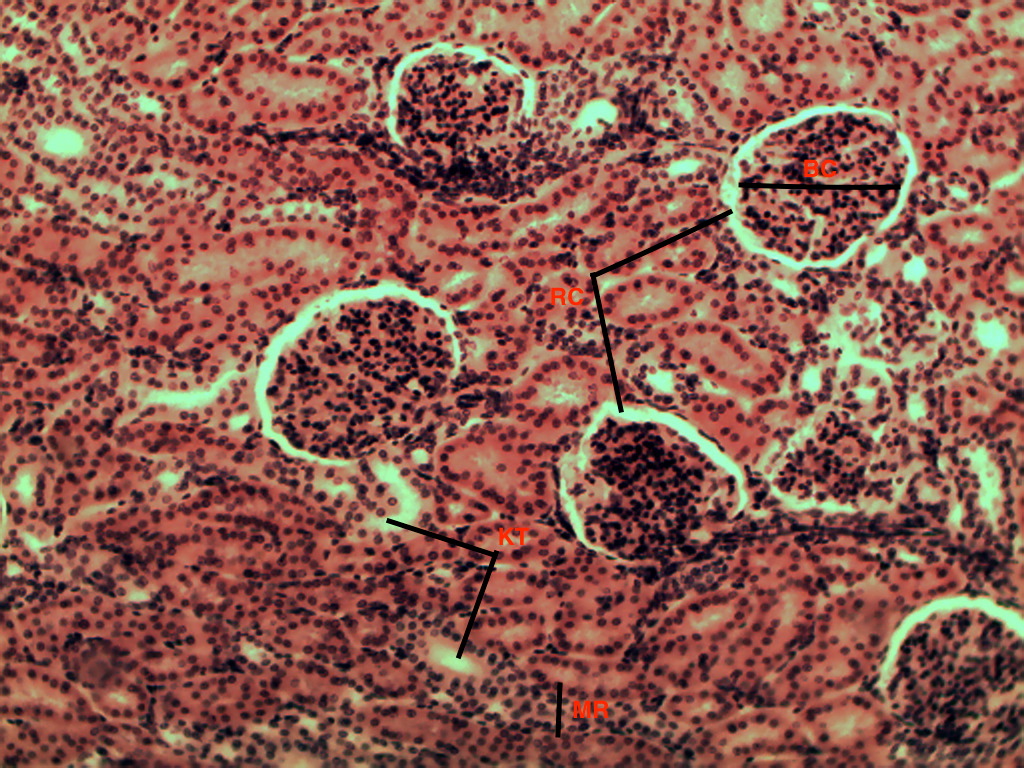

Microscopic observations of H&E stained kidney sections (400 × Kidney Microscope Slide Labeled in this virtual slide of kidney you should be able to identify. histology of connective tissue (capsule, cortex, medulla) in a kidney stained with azan. The outer region or renal cortex, containing many small, round renal corpuscles, much of the. describe the histology of the proximal convoluted tubule, nephron loop, distal convoluted tubule, and collecting duct. The. Kidney Microscope Slide Labeled.